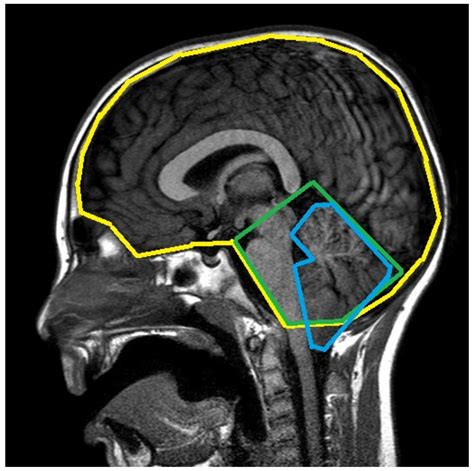

When conservative methods fail or when the anatomy presents a clear threat to neurological health, surgical intervention becomes the primary path. The most common and effective of the Chiari malformation treatments is a procedure known as posterior fossa decompression. The goal of this surgery is to create more space for the cerebellum and allow for the normal flow of cerebrospinal fluid (CSF).

Posterior Fossa Decompression Removal of a small portion of bone at the back of the skull. Reduce pressure on the cerebellum and restore normal CSF flow.

Dural Opening (Duraplasty) Expanding the covering of the brain. Provide extra space for the brain to sit comfortably without compression.

During a typical decompression surgery, the surgeon removes a small piece of bone from the base of the skull and sometimes a small part of the top of the spinal canal. Often, the surgeon will also open the dura mater (the thick covering over the brain) and sew in a graft to enlarge the space, a process called duraplasty. This is considered the gold standard among Chiari malformation treatments because it directly addresses the cause of the compression.